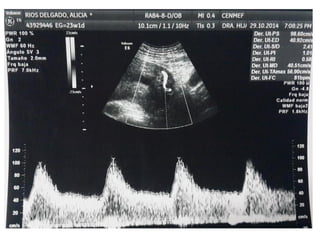

DUCTUS VENOSO

• Vaso pequeño que conecta la vena umbilical con la

proximidad de la aurícula derecha. Tiene un papel crítico

dirigiendo la sangre oxigenada al cerebro fetal

• Un 20% de la sangre oxigenada de la placenta sobrepasa el

hígado y se dirige al corazón fetal. Entra en la aurícula

derecha y luego a la izquierda, a través del foramen oval.

• De la aurícula izquierda pasa al ventrículo izquierdo y luego

a la aorta

VALORACIÓN DV

• Semanas 11+0-13+6 y la LCC entre 45-84 mm. El feto no

debe moverse.

• El tamaño de la imagen debe ser tal que el tórax y abdomen

fetal ocupen toda la pantalla. Se debe obtener un corte

sagital medio del tronco fetal.

• Se debe usar el Doppler color para demostrar la vena

umbilical, el ductus venoso y el corazón fetal. La ventana

del Doppler pulsado debe ser pequeña (0,5-1,0 mm) y debe

situarse en la zona de aliasing normalmente en amarillo

• El ángulo de insonación debe ser menor de 30 grados.

• El filtro debe ser de baja frecuencia (50-70 Hz), para

permitir la visualización de la onda completa.

• La velocidad de barrido debe ser alta (2-3 cm/s), para

obtener una forma más ancha y poder evaluar mejor la onda

A.

DUCTUS VENOSO • Vasopequeño que conecta la vena umbilical con la proximidad de la aurícula derecha. Tiene un papel crítico dirigiendo la sangre oxigenada al cerebro fetal • Un 20% de la sangre oxigenada de la placenta sobrepasa el hígado y se dirige al corazón fetal. Entra en la aurícula derecha y luego a la izquierda, a través del foramen oval. • De la aurícula izquierda pasa al ventrículo izquierdo y luego a la aorta

VALORACIÓN DV • Semanas11+0-13+6 y la LCC entre 45-84 mm. El feto no debe moverse. • El tamaño de la imagen debe ser tal que el tórax y abdomen fetal ocupen toda la pantalla. Se debe obtener un corte sagital medio del tronco fetal. • Se debe usar el Doppler color para demostrar la vena umbilical, el ductus venoso y el corazón fetal. La ventana del Doppler pulsado debe ser pequeña (0,5-1,0 mm) y debe situarse en la zona de aliasing normalmente en amarillo

VALORACIÓN DV • Elángulo de insonación debe ser menor de 30 grados. • El filtro debe ser de baja frecuencia (50-70 Hz), para permitir la visualización de la onda completa. • La velocidad de barrido debe ser alta (2-3 cm/s), para obtener una forma más ancha y poder evaluar mejor la onda A.